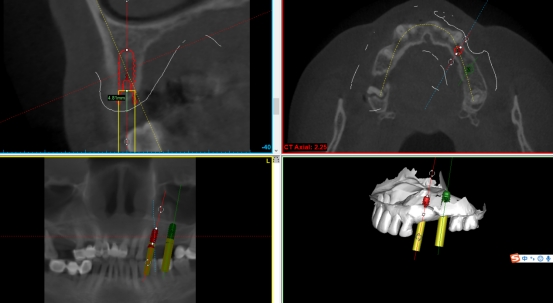

第二步:数据匹配

(CBCT采集的Dicom数据与口扫获取的STL数据进行匹配,通过牙齿位点进行匹配。)

第三步:植入及导板设计

第四步:导板制作完成